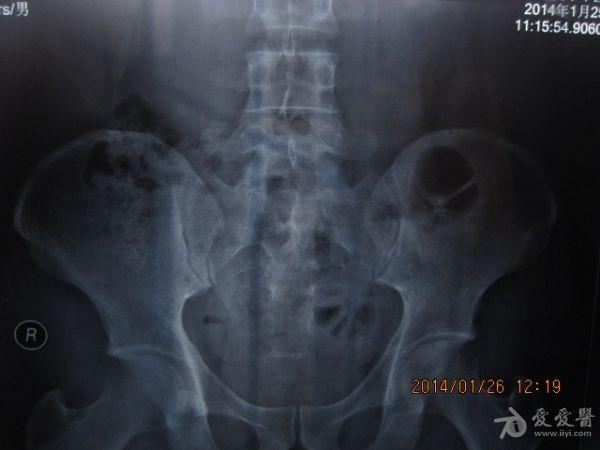

请老师看看这个腰椎和盆骨的平片有无问题

摔了一跤右臀着地,同时闪到腰,查出有椎间盘突出,目前是右臀麻木,整个右腿酸胀沉重。肌力正常走路正常,坐不到5分钟右腿就酸胀难忍。明显觉得左右**感觉不一样,右边软得多,

自觉下腰和盆骨感觉别捏,有歪斜感,扭腰时觉得舒服。腰4右侧一下有异物感。今天照了个腰椎正侧位和盆骨的正位平片,医生说没什么问题,拿来请各位老师看看腰椎和盆骨有没有错位,旋转,不等高等情况,再次感谢。

照该片看应该是骨盆旋移

这种症状拍平片没有什么意义,选择MRI或者CT吧

看片子没发现什么大的问题,没有骨折,没有增生。腰椎间盘突出做核磁共振最清楚。